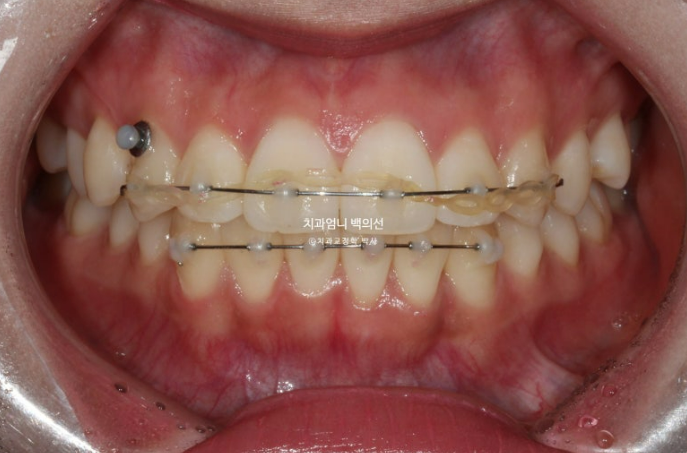

치료시작 9개월째 모습입니다.

앞니 사이 미세한 틈을 없애기 위한 파워체인 고무줄을 걸고

사진에 보이는 고리끼리는 환자분이 스스로 뺐다 꼈다 하는 고무줄을 걸며 중심선과 좌우 교합까지 맞춥니다.

그러다보니 어느덧 9개월이라는 시간이 흘렀습니다.

MTA 장치는 송곳니부터 송곳니까지 앞니에만 붙여서 배열을 진행했고 나머지 작은어금니와 큰어금니는 움직이지 않았습니다.